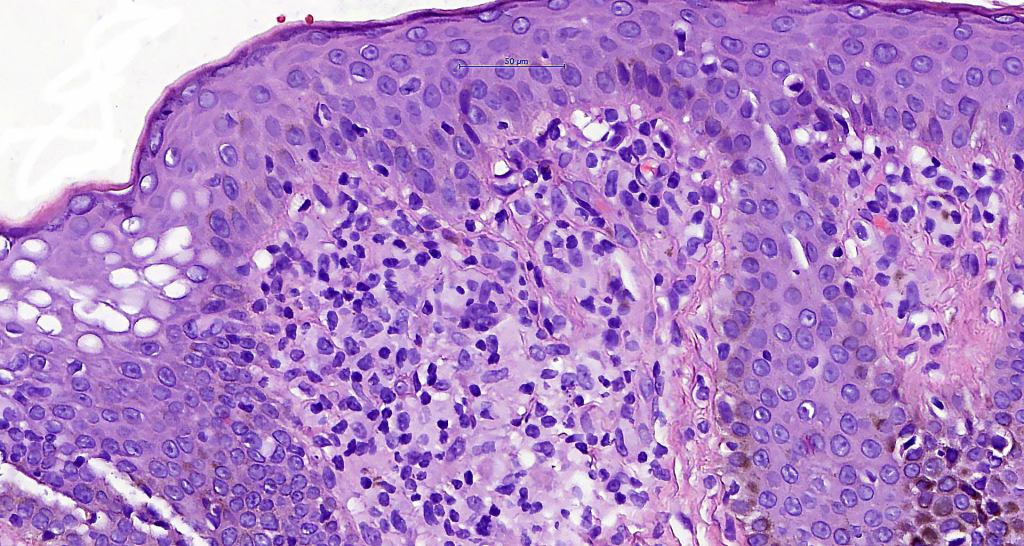

Histological features

•Variable histological features ranging from a non-specific superficial perivascular or band-like dermal infiltrate with minimal or no epidermotropism through to mycosis fungoides-like histology; can mimic atopic dermatitis

•Sézary cells are CD45RO, CLA, CD158 & CD4+

.Loss of CD7 (40% or more) & CD26 (30% or more)

•Variable loss of CD2, CD3 & CD5